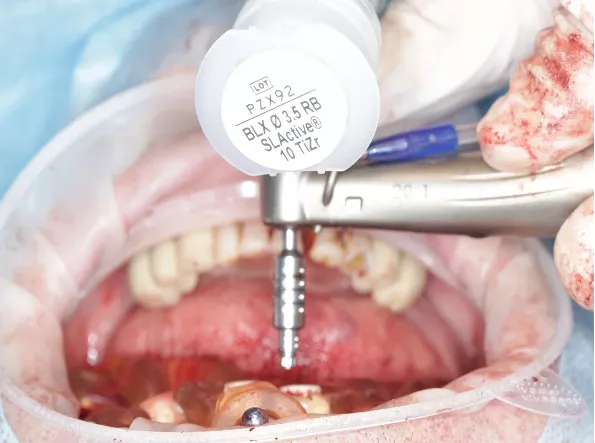

Fully guided surgery was performed using the second guide. Implants were placed at sites

14 - Straumann BLX 4.0 x 12 mm

12 - Straumann BLX 3.5 x 10 mm

22 - Straumann BLX 3.75 x 10 mm

24 - Straumann BLX 3.5 x 12 mm

All implants were torqued to ≥35 Ncm (Figs. 28-30), (Video 3).